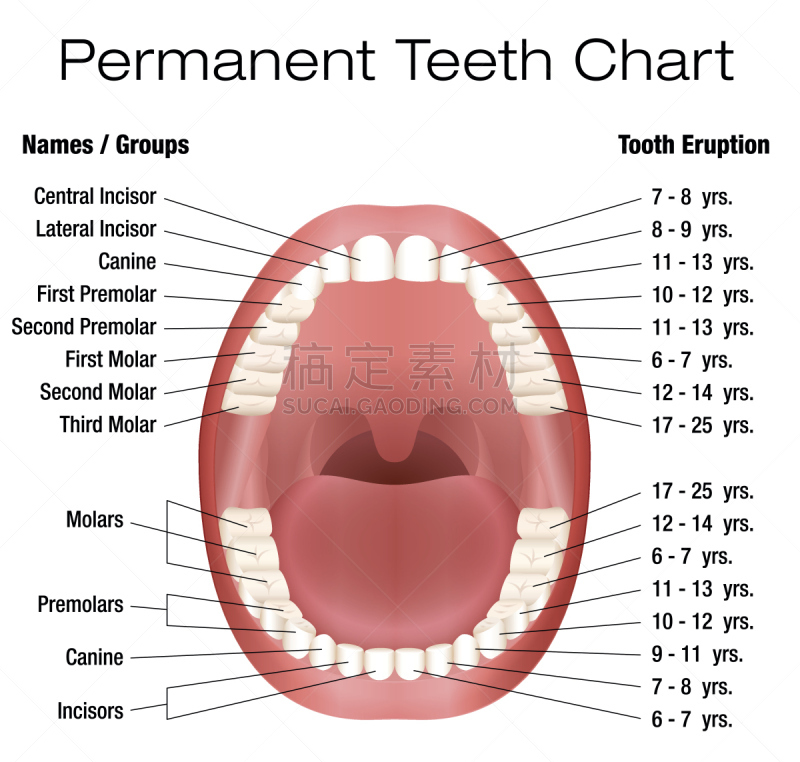

成人牙齿的名字详情

EPS